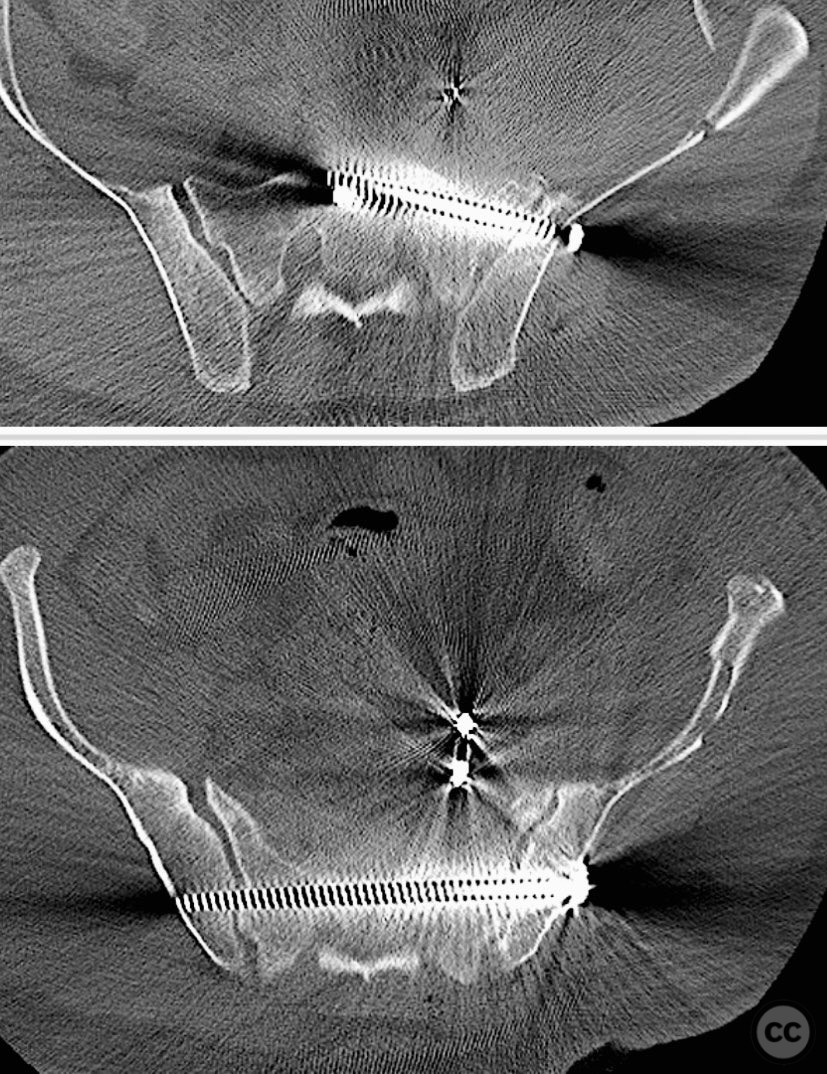

Anatomical surgical approach:  The anterior approach utilized a Pfannenstiel incision to access the symphysis pubis and pubic rami, with subperiosteal dissection of the rectus abdominis and exposure of the retropubic space for reduction and fixation. For posterior sacral ORIF, a midline longitudinal incision was made over the sacrum, with subperiosteal elevation of the paraspinal musculature to expose the sacral fracture. A tenaculum clamp was applied for direct reduction, followed by percutaneous insertion of iliosacral screws under fluoroscopic guidance.

The case was notable for initial successful multidisciplinary management of both hemodynamic instability and intraperitoneal bladder injury, allowing for staged surgical intervention. Despite accurate anterior pelvic reduction and fixation, postoperative imaging revealed worsening posterior sacral displacement, necessitating subsequent posterior open reduction. The use of a tenaculum clamp facilitated direct anatomical reduction of the sacral fracture prior to iliosacral screw fixation. The presence of an embolic coil from prior angioembolization did not impede surgical access or hardware placement. This case demonstrates that initial anterior pelvic ORIF does not complicate or preclude subsequent routine posterior pelvic ORIF in complex unstable ring injuries.

Orthopaedic implants used:   Anterior pelvic reconstruction plate, iliosacral cannulated screws, tenaculum reduction clamp